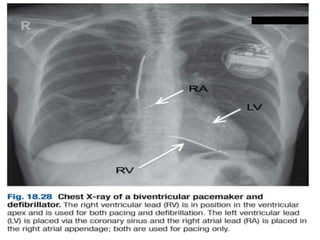

Implantable cardiac defibrillators

:and resynchronisation therapy

 Patients with symptomatic ventricular

arrhythmias and heart failure have a

very poor prognosis.

 Irrespective of their response to anti-

arrhythmic drug therapy, all should be

considered for implantation of a cardiac

defibrillator.

 In patients with marked intraventricular

conduction delay, prolonged

depolarisation may lead to

uncoordinated left ventricular

contraction.

 When this is associated with severe

symptomatic heart failure, cardiac

resynchronisation therapy should be

considered.

 Here, both the LV and RV are paced

simultaneously in an attempt to

generate a more coordinated left

ventricular contraction and improve

cardiac output.